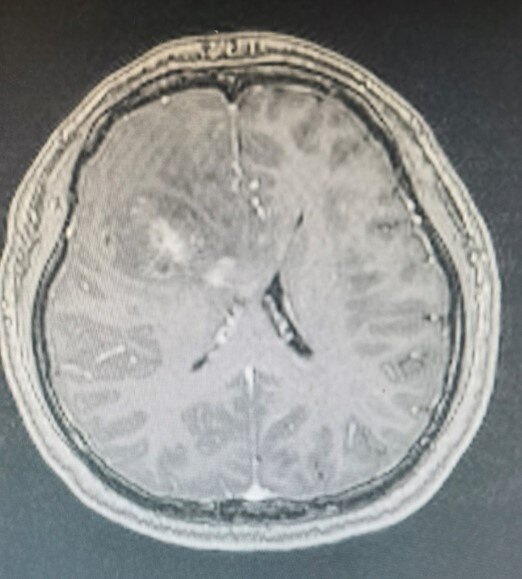

术前增强T1